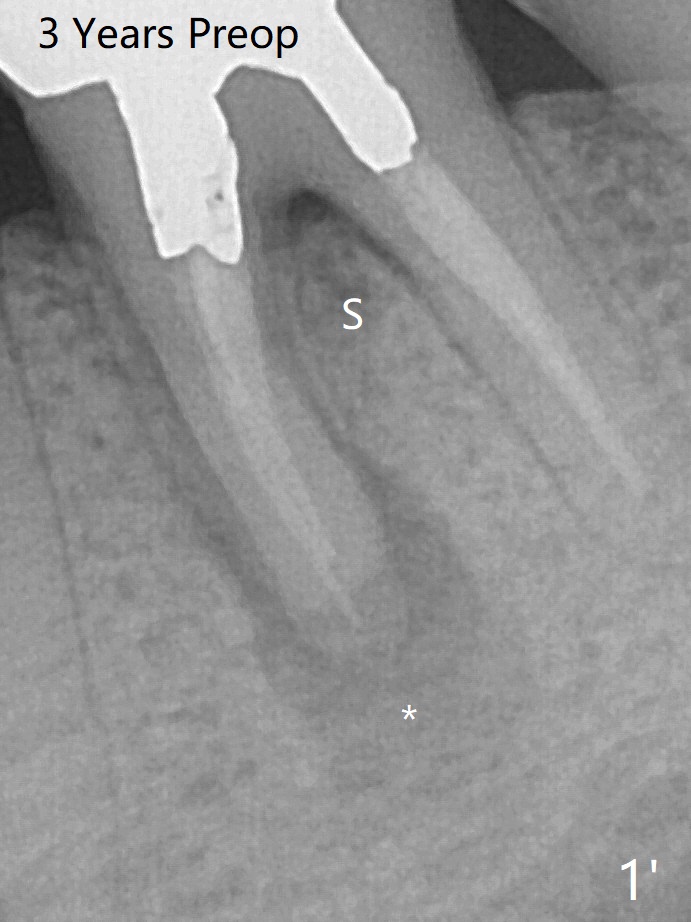

When the patient returns for #15 comp, the bone resorption and swelling at #19 are worse than those 3 years ago (Fig.1,2).  53岁男三年来左下六反复感染(图一,二)。